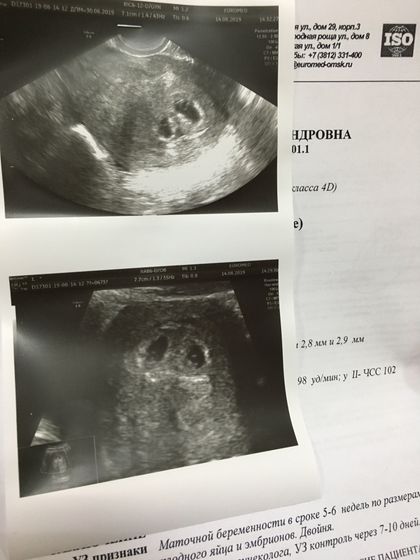

Сходили сегодня с мужем на УЗИ, все хорошо? Только вот мы сразу станем многодетной семьей? Муж радуется, а я просчитываю дальнейшие действия и расходы? Это стало большой неожиданностью для нас? Но ничего, прорвёмся!????

Двойня???)мамочки вот это поворот)))желаю мамочке терпения и побольше сил????????

Спасибо, я вообще об этом не думала? Только вот как забеременела мне муж начал про двойню говорить, да и я над подругой пошутила, что Двойня будет. А тут бац, реально двойня? теперь главное выносить????